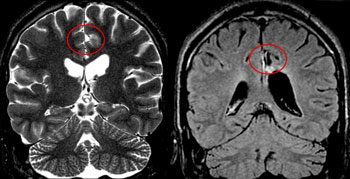

Magnetresonanz-Aufnahmen eines Patienten mit fokaler kortikaler Dysplasie vor (links) und nach der Operation. Blick von hinten auf das Gehirn. Bildquelle: Universitätsklinikum Freiburg.